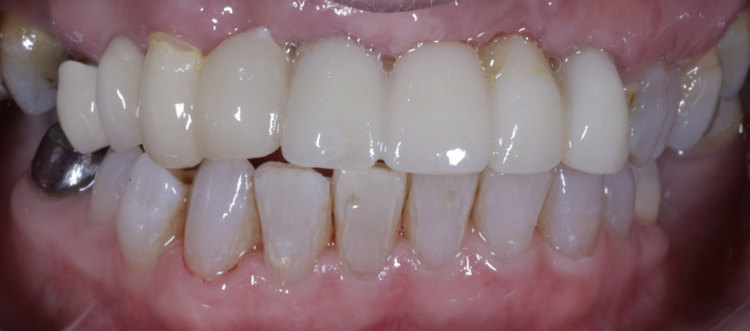

Dr Omar Iqbal replaces a patient’s failing bridge in the aesthetic zone with a new prosthesis fixed in place with two Tapered Pro Conical implants.

A 61-year-old female patient presented with a failing, upper 3-3, metal ceramic bridge, connected to the canines and lateral incisors on either side. The bridge had failed with caries and core fractures on both abutment teeth on the patient’s left side. As such, the patient was keen to repair or replace the bridge without the use of a removable prosthesis at any point during treatment.

The patient returned to the practice for review two weeks post-surgery and to confirm successful and otherwise uneventful healing. Discomfort was minimal and she reported being very satisfied with the outcome. After a healing period of three months, the patient returned to begin making the final prosthesis. Good soft tissue adaptation was noted around the temporary prosthesis and the buccal contour was successfully maintained.

Upon professional reflection, this case went according to plan, emphasising the importance of meticulous assessment and preparation prior to implant surgery. The guided approach helped to ensure the precise positioning of the implants which facilitated connecting the temporary bridge. This, alongside the implant selection, was crucial for maximising on the limited bone available for primary stability.